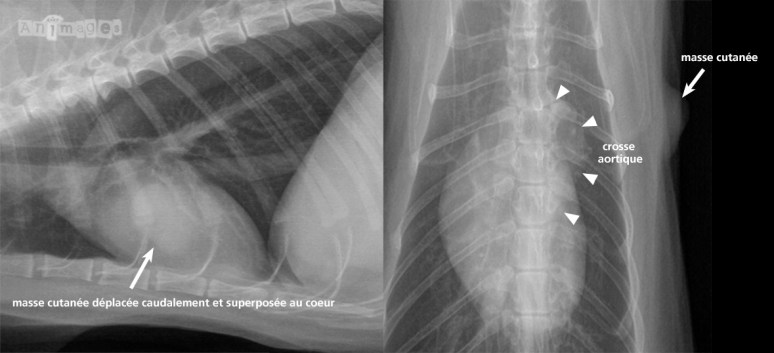

Cette tache sur le coeur, c’est la petite masse sur la peau

Ahhhh, ce vilain jeu des superpositions ! L’opacité arrondie et bien définie superposée à la silhouette cardiaque était attribuée à la petite masse cutanée du côté gauche. Selon les réponses au quiz, la majorité d’entre vous semble avoir vu juste. Bravo ! Pour les autres, dites-vous que nous sommes tous passés par là… et ça nous arrive encore ! 😉 La proéminence de la crosse aortique peut en voir déjoué certains. Cette trouvaille est fréquente chez les vieux chats et possiblement davantage chez les hyperthyroïdiens et/ou hypertendus, bien que ça n’a pas vraiment été démontré, du moins pas à ma connaissances. Cette déformation de l’aorte proximale est aussi souvent accompagnée d’une silhouette qui s’allonge sur le sternum. Dans ce cas-ci, la silhouette était aussi allongée en raison d’une augmentation de volume du coeur gauche, vraisemblablement associée à l’hyperthyroïdie. Les vaisseaux sont normaux (bien effilés et à peine visible en périphérie) et le parenchyme ne montre aucun signe d’oedème.